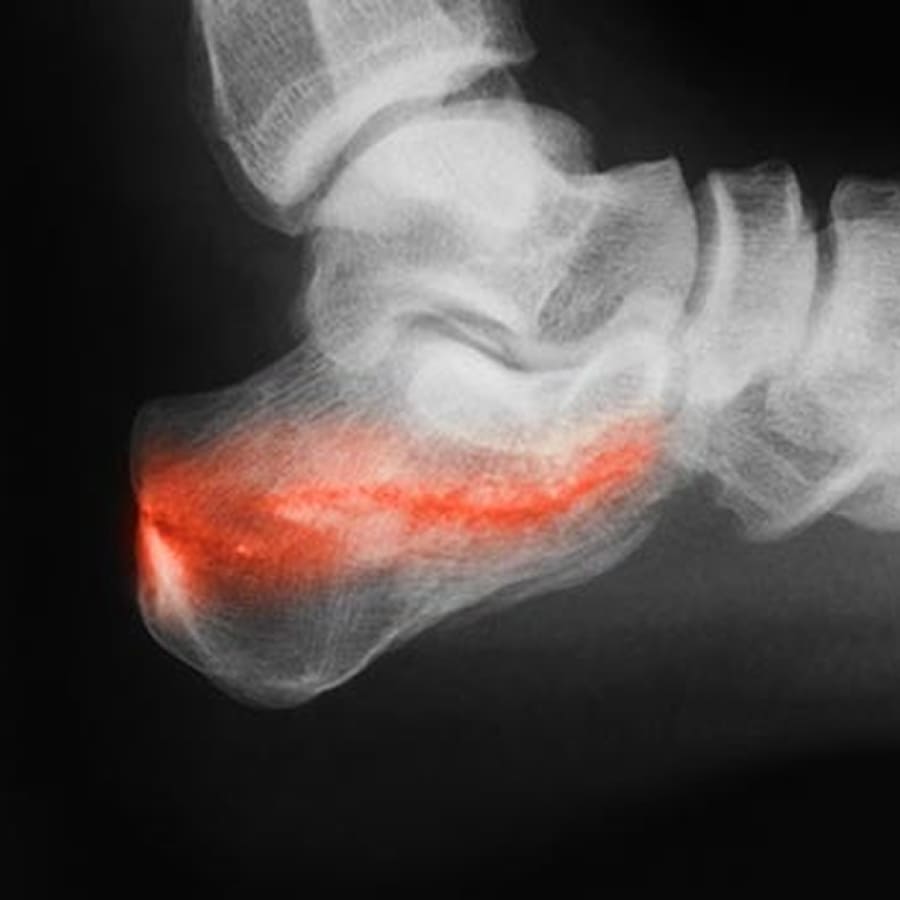

Como a microfratura óssea é diagnosticada?

O diagnóstico geralmente inclui a avaliação clínica com ortopedista e exame físico detalhado. Também é necessário realizar radiografias iniciais e/ou ressonância magnética (o exame mais sensível para microfraturas), para confirmar o diagnóstico e determinar o protocolo de tratamento mais indicado para cada caso.